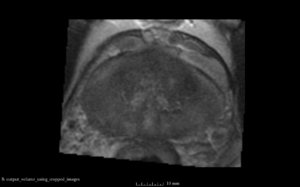

We used this sample data with Reader 1 segmentations to visually evaluate differences in the registration results. All three results of BRAINSFit with ITKv3 in Slicer 3.6 look reasonable. Using BRAINSFit with ITKv4 in Slicer 4.4 creates a reasonable result for Case 7, but look strongly distorted towards the edges of the bounding box in Case 8 and 9.

Case 9

Reference intraop volume

Reg Result Slicer 3.6 with ITKv3

Reg Result Slicer 4.4 with ITKv4